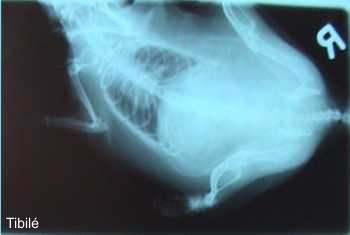

Binnenstebuitenfoto

Tarkan: Tibilé moest op de foto bij de dierenarts, omdat hij bloed plaste. Ik had  nog gezegd dat hij zich heel goed moest wassen voor de foto, maar daarvoor was Tibilé veel te moe. Gelukkig maar dat er een binnestebuitenfoto werd gemaakt, want dan maakt het niet uit hoe je haar zit. En omdat Tibilé zo moe was, hoefde hij geen narcose.

Tibilé: Ik was wel heel moe toen we terugkwamen van de dierenarts, maar ik heb wel weer gegeten. Ook heb ik heerlijk bij de baasjes op schoot gelegen, maar ik vind het niet leuk als ze me in de kooi zetten. Dan spartel ik heel erg tegen.

Tarkan:

Ik wist trouwens niet dat Tibilé er van binnen zo raar uitziet. De baasjes zeggen dat alle ratten er van binnen zo uitzien, maar ik geloof daar niets van.